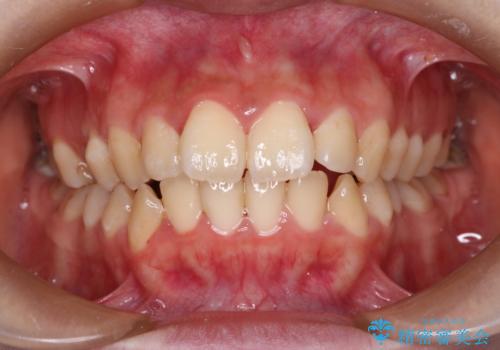

- 口元が出ていることを主訴に来院されました。

歯を抜いてスペースを作ることで、前歯を下げることができました。

ハーフリンガルということで治療期間が3年近くかかりましたが、口元もしっかり下がり満足していただきました。